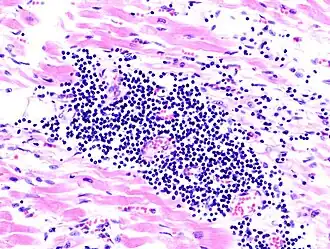

- Biopsie de myocarde : la biopsie objective une infiltration du myocarde par les lymphocytes ou quelquefois par les macrophages, une autre variété de globules blancs. Elle est accompagnée d'autre part d'une multiplication des cellules conjonctives avec parfois nécrose. L'élément clé reste la biopsie du myocarde, faite par voie endovasculaire : un cathéter comportant une pince à son extrémité est introduite dans le ventricule droit par l'intermédiaire de la veine fémorale, sous contrôle radiologique et sous anesthésie locale (biopsie endomyocardique). Elle est réservée aux cas graves avec insuffisance cardiaque d'apparition récente[5]. Elle permet l'isolement et l'identification du virus responsable.